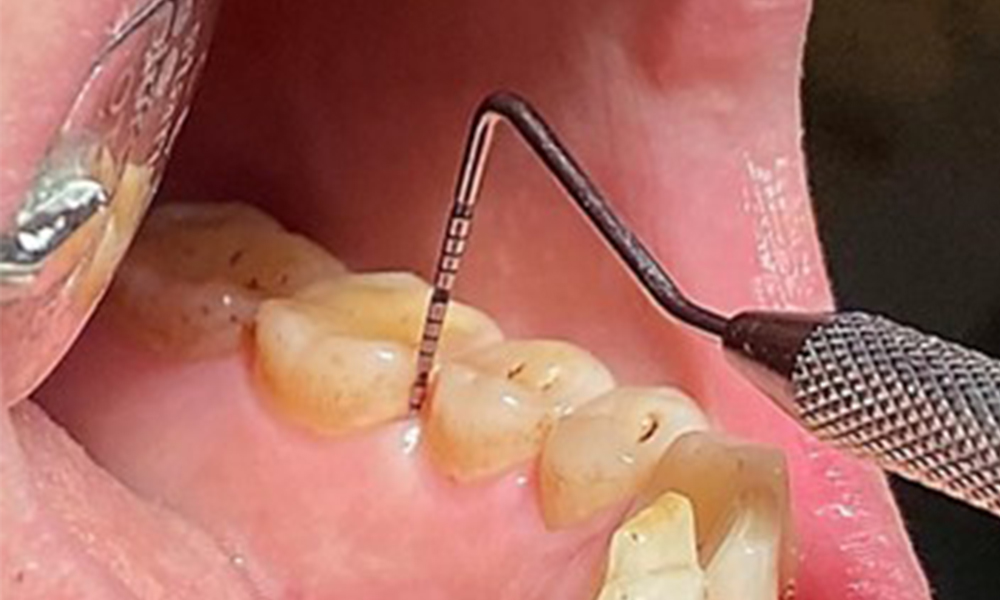

Due to the otherwise favourable general medical condition, the needs determined during the intraoral examination will be decisive for their treatment. It will be essential to periodically determine the probing depths. Gingival bleeding decreases in smokers, which is why the clinical diagnosis of periodontitis can only be made by probing (Fig. 7). Placing exclusive focus on the determination of bleeding indices may obscure existing periodontitis or gingivitis. (5)

- It is important to document findings during the therapeutic appointment. Bleeding-on-probing (BOP) status to measure periodontal pocket depth in the early stages of disease must be determined during each appointment. This is particularly important in smokers due to decreased tissue perfusion.